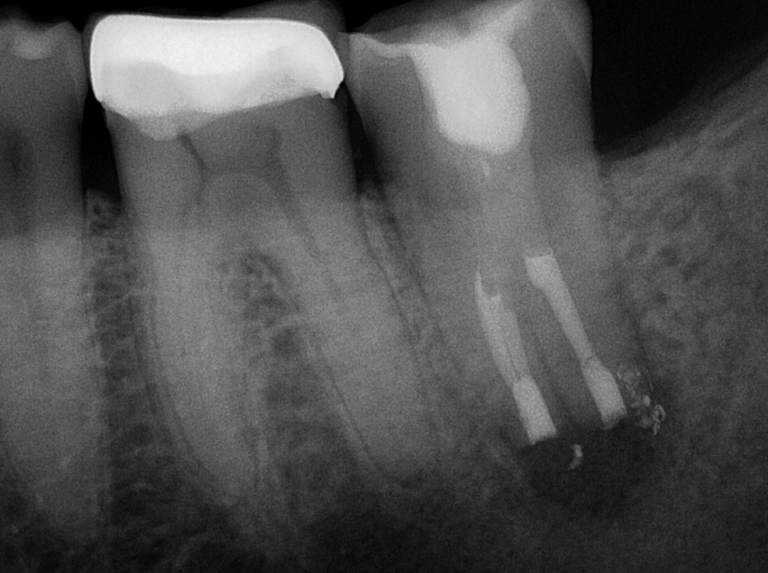

Thorough diagnostic testing and x-ray (radiographic) imaging will be completed to ensure an endodontic problem exists and if it’s the tooth with previous root canal treatment. Additionally, Cone Beam CT 3D imaging will be required to help identify the cause of failure, and to give exact and proper measurements needed for the procedure. Your medically history will also be thoroughly reviewed. The prognosis and description of intentional replantation will then be explained to you.

The tooth is then placed in a specialized solution to keep the roots and ligament hydrated. The small, infected portion of the roots are removed. Next, the root ends are prepared and filled with a specialized material, sealing the roots. These steps are completed efficiently and promptly, as working time needs to be kept to a minimum to prevent dehydration of the tooth and ligament, and thus achieve an optimal outcome.

The treated tooth is now placed back in the socket (replanted) in its original position. Sutures, or a splint, may be placed to keep the tooth in position. It is important to bite on gauze for the rest of the day to aid in keeping the tooth in the socket.

Treatment Completed by Dr. Battista